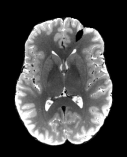

Refer to captionRefer to captionRefer to captioninitializationOptimal TransportRefer to captionRefer to captionRefer to captionOptimal Transport (blurred)Refer to captionRefer to captionRefer to captionMultilevelRefer to captionRefer to captionRefer to captionoptimizedRefer to captionRefer to captionRefer to captionRefer to captionRefer to captionRefer to caption

Figure 6: Example field maps (Subject ID 826353) at initialization (top row) and after optimization with Gauss-Newton (bottom row). The first column uses the proposed optimal transport initialization scheme. The middle column uses the same scheme with an additional Gaussian blur to promote smoothness. The right column uses the coarse-to-fine multilevel initialization scheme from HySCO with five levels, and the final field map is optimized at the original image resolution. The multilevel initialized field map is smooth by construction and further optimized to improve the relative image distance at the full resolution. The optimal transport initialization accurately corrects the distortions but is not smooth in the non-distortion dimensions unless blurred with a Gaussian. After the fine-level optimization all field maps are visually similar.